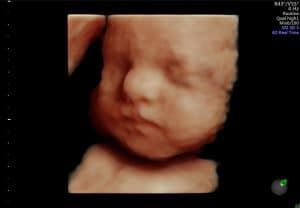

Nadat de baby met een 2D echo in beeld is gebracht en de ligging duidelijk is, wordt er met een 3D echo extra kleur aan de doorsnede toegevoegd. Je ziet dan drie dimensies (3D), namelijk lengte, breedte en diepte. Waar je met een 2D echo als het ware door je kindje heen kijkt, kijk je er met een 3D echo omheen. Dus alles wat bijvoorbeeld voor het gezichtje van de baby ligt is met een 3D echo wel te zien. Door de 3D beelden te combineren met 4D echografie, krijg je bewegende 3D beelden. Dit maakt het een ‘live’ ervaring om naar je kindje te kijken.

De foto’s die je vaak op internet ziet en ook op deze site zijn optimale beelden. Dan bedoelen we een zeer gunstige ligging van de baby, slanke zwangere en mogelijk niet de eerste zwangerschap, waardoor de wand van de baarmoeder soepeler is. Zie deze foto’s dus niet als vergelijking voor je eigen 3/4D-echo.